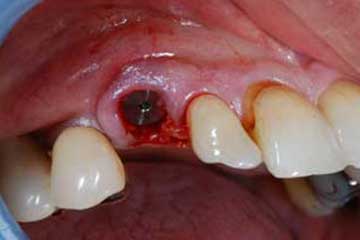

Impianto post-estrattivo

In un paziente cardiopatico di 72 anni